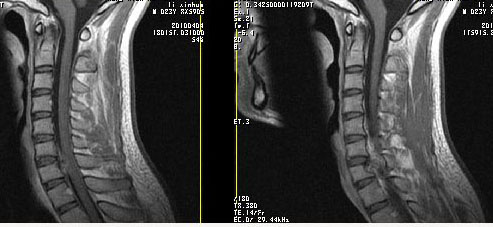

男24岁因一年来感头昏,查体四肢肌力及感觉无异常。颈椎dr未见异常,mri发现c7水平段椎管内左侧占位。患者于7年前有车祸伤病史(但是未检查,自述无异常)。请讨论是否是机化血肿或骨折片,能除外是肿瘤?

椎管内骨性肿块,与第7颈椎左下关节突关系密切,向椎管内生长,第7颈椎椎体左后缘受压变形,边缘可见硬化边,与肿块间间隙清晰。mri扫描肿块内可见骨髓信号,考虑骨软骨瘤可能性大。

考虑c7左侧椎弓根部骨软骨瘤。